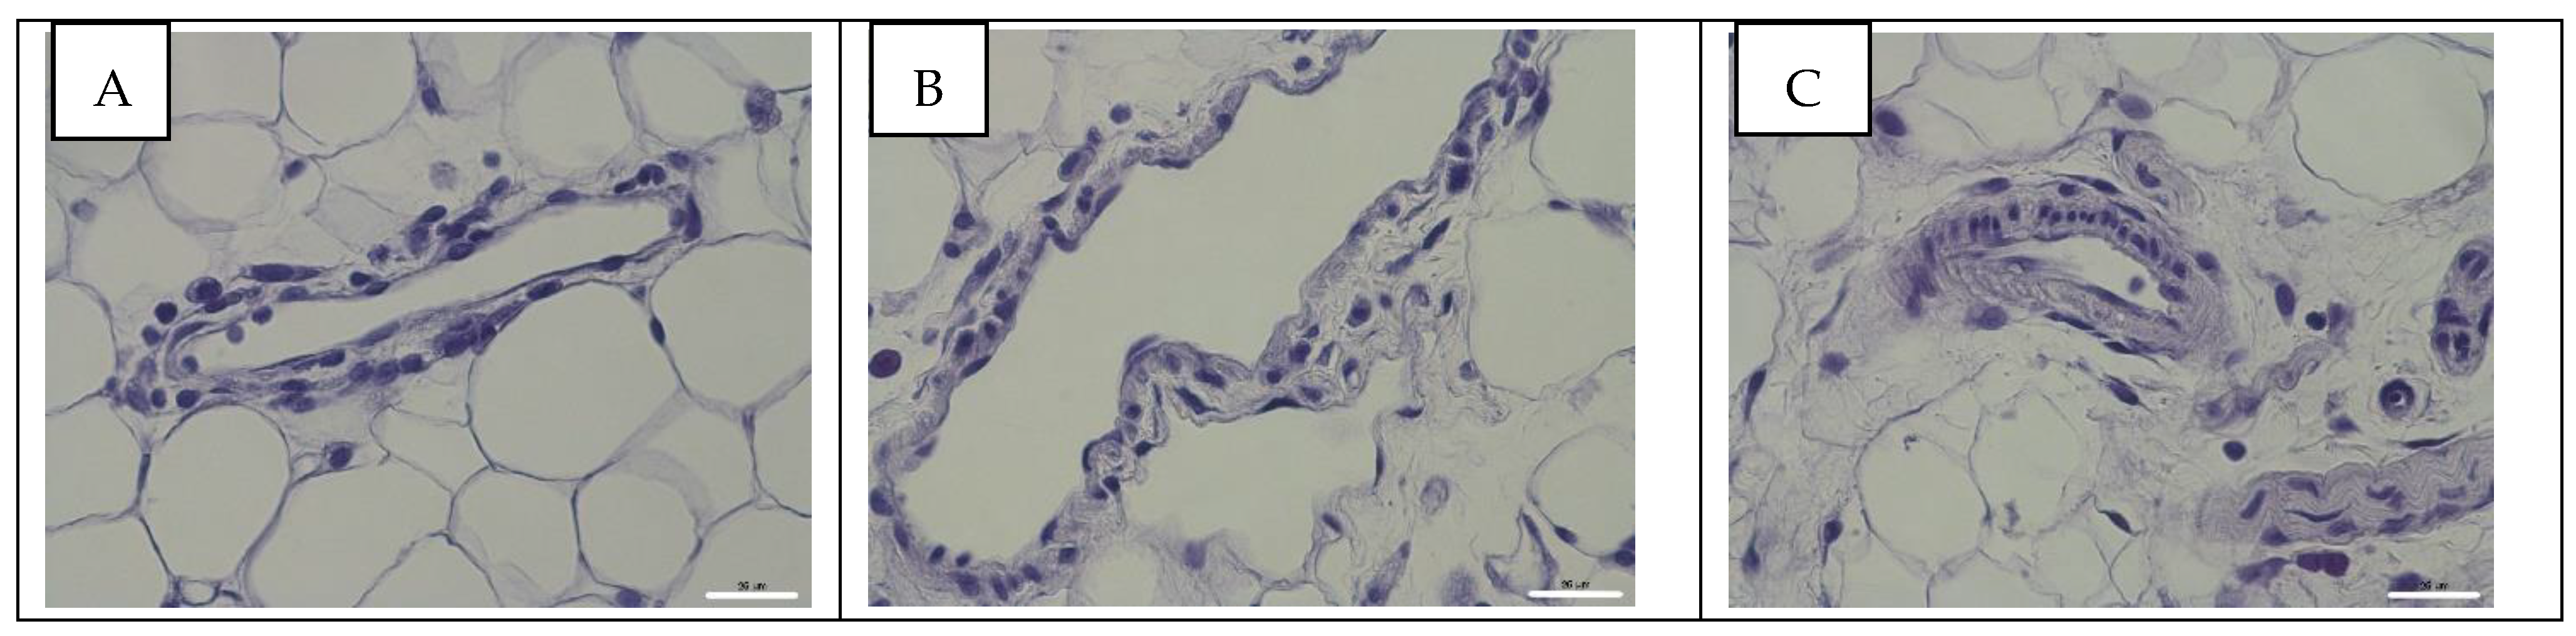

3.4. Detection of Influenza A Virus NP Antigen in Pulmonary and Mesenteric Tissues and Blood Vessels